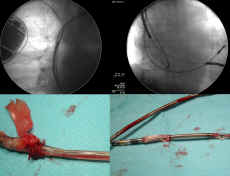

C. W elektrodach defibrylatorowych, w których przebiega

wiele przewodów (dwa do stymulacji/sterowania) dwa do

proksymalnego uzwojenia defibrylującego i ewentualnie dwa

do uzwojenia proksymalnego - objawy zależą od liczby odsłoniętych

przewodów. Najburzliwsze objawy powoduje uszkodzenie

obwodu "pacing/sensing" gdyż

"trzaski" są powodem nieadekwatnych (czasem

licznych) interwencji wysokonapięciowych. Towarzyszą im

różnego stopnia nieprawidłowości z zakresie spadku

amplitudy odbieranego potencjału wewnątrzsercowego, obniżenia

(często wahania) oporności poszczególnych obwodów bądź

wzrostu progu stymulacji.